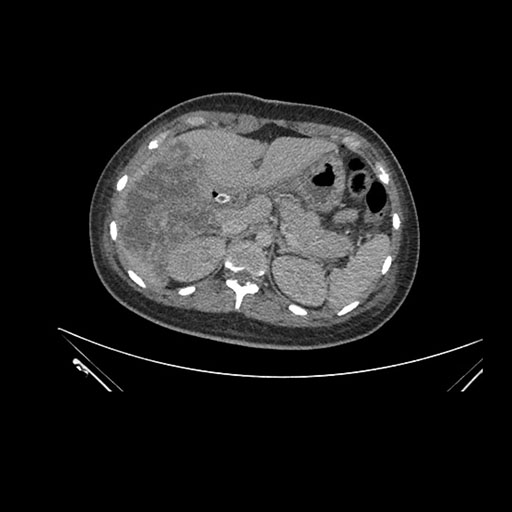

Axial Venous